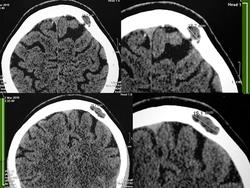

Арахноидальная киста

ID: 22682 Arachnoid cyst Dr David Ferreira - 16 Apr 2013 These images are compatible with an arachnoid cyst, which is commonly an...

В первом (зеленом) наборе изображений, как-то не арахноидальная киста, больше на пахионовую грануляцию похоже.